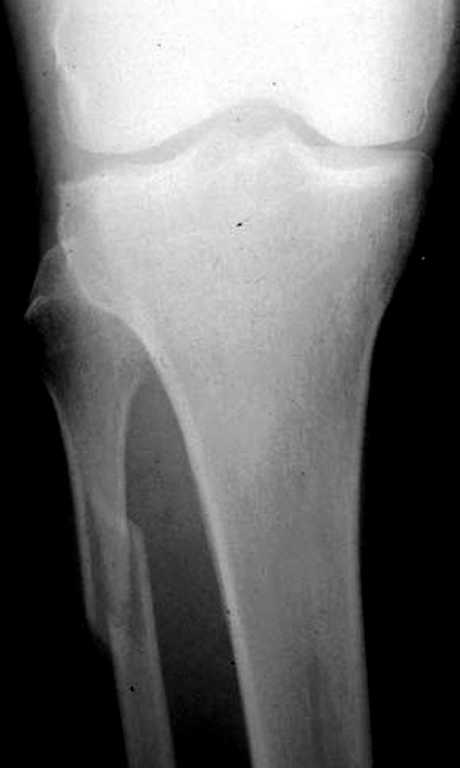

При проксимальных переломах малоберцовой автоматически необходимо подозревать повреждение синдесмоза - Maisonneuve Fracture.

"На западе", как правило, при переломах голеностопа требуются снимки проксимальной части голени.

Описанное в 1840 году Maisonneuve повреждение характеризуется тем, что при фиксированной наружной ротации стопы повреждается передняя фибуло-тибиальная связка, часть синдесмоза, с переломом медиальной лодыжки и без, дальше разрыв продолжается по межкостной мембране и спиральный или косой перелом малоберцовой происходит выше.

Для уточнения диагноза надо сделать все стандартные снимки голеностопа, (несмотря на необходимость при любых повреждениях голеностопа, почему-то очень трудно воспроизводится коллегами из СНГ?)

На прямой проекции можно увидеть расширенную медиальную щель, и на мортизе укорочение малоберцовой.